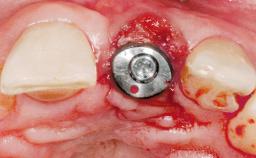

A 30-year-old female patient had lost tooth 21 and was referred to our clinic for consultation and treatment. Due to advanced apical infection, tooth 21 had been extracted two months earlier at another clinic and an acrylic-resin tooth had been bonded to the adjacent teeth. The patient desired implant treatment to avoid any damage to the adjacent natural teeth. While the patient had no history of any systemic disorder, she was a heavy smoker and exhibited medium to advanced periodontitis in the entire jaw. After the initial treatment to achieve a pocket probing depth of less than 4 mm and no bleeding on probing, a decrease in the height of the papillae mesial and distal to the extraction site and overall gingival recession were observed.

Type of Implants One-Piece|Reduced-Diameter

Attachment One-Piece|Reduced-Diameter

Bone Augmentation Horizontal|Staged

Augmentation Materials Autogenous chips|Membrane

Soft Tissue Grafting Simultaneous